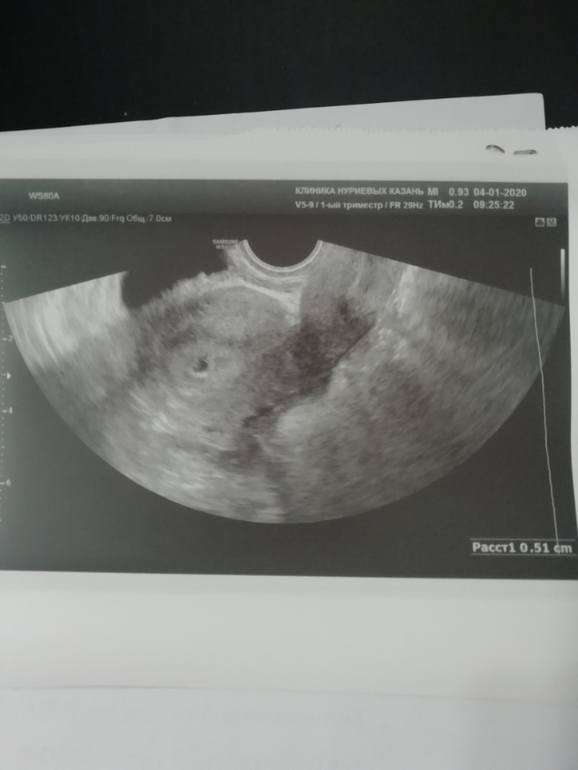

Девочки, здравствуйте! 22 декабря хгч был 91.Сегодня пошла на узи, сказали замершая беременность. Сразу сдала хгч, результат 741.Узист сказала, что всё уже хочет выйти, но почему-то не может. Я говорю, что утрожестан ставлю. Она сказала о меняй, всё выйдет. Плодное яйцо маленькое. Позвонила Г, она отправляет на чистку. Последние М были 16.11 Что делать а? Ничего ещё сообразить не могу. Страшно....

Для 8 недель на узи есть пя и эмбрион +сб, а у вас точка и хгч низкий. У меня хгч был 6000 и такая точка. Так что увы, сочувствую. Я отменила дюфастон и все вышло само на то время уже и была мазня. Чистка не нужна была

Мне кажется врач права, беременность не развивается,хгч слишком мал для вашего срока и пя соответствует 5 неделям акушерским,да и динамика не очень,22.12 -91 ,и сегодня 4.01 -741 прирост очень медленный или он уже падает или не вырос, сочувствую,но тут уже ничего не сделать,сил вам)